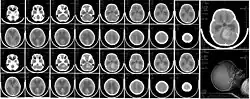

CT scan, showing a tumorous mass in the posterior fossa, giving rise to obstructive hydrocephalus, in a six-year-old girl